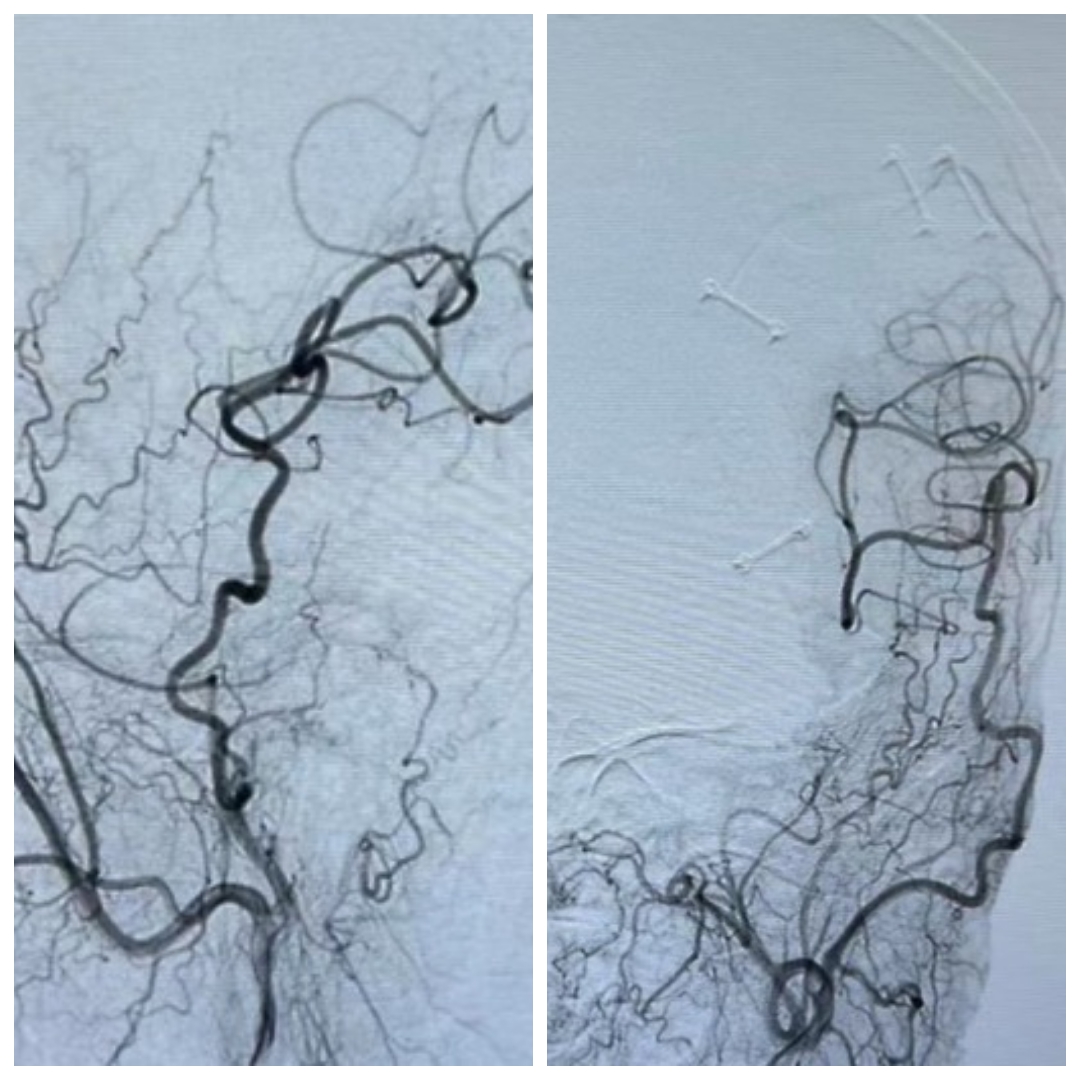

半年后患者来我科复查DSA。颞浅动脉与M4血管吻合满意,颈外动脉造影可见大脑中动脉显影,天堑造通途。。。